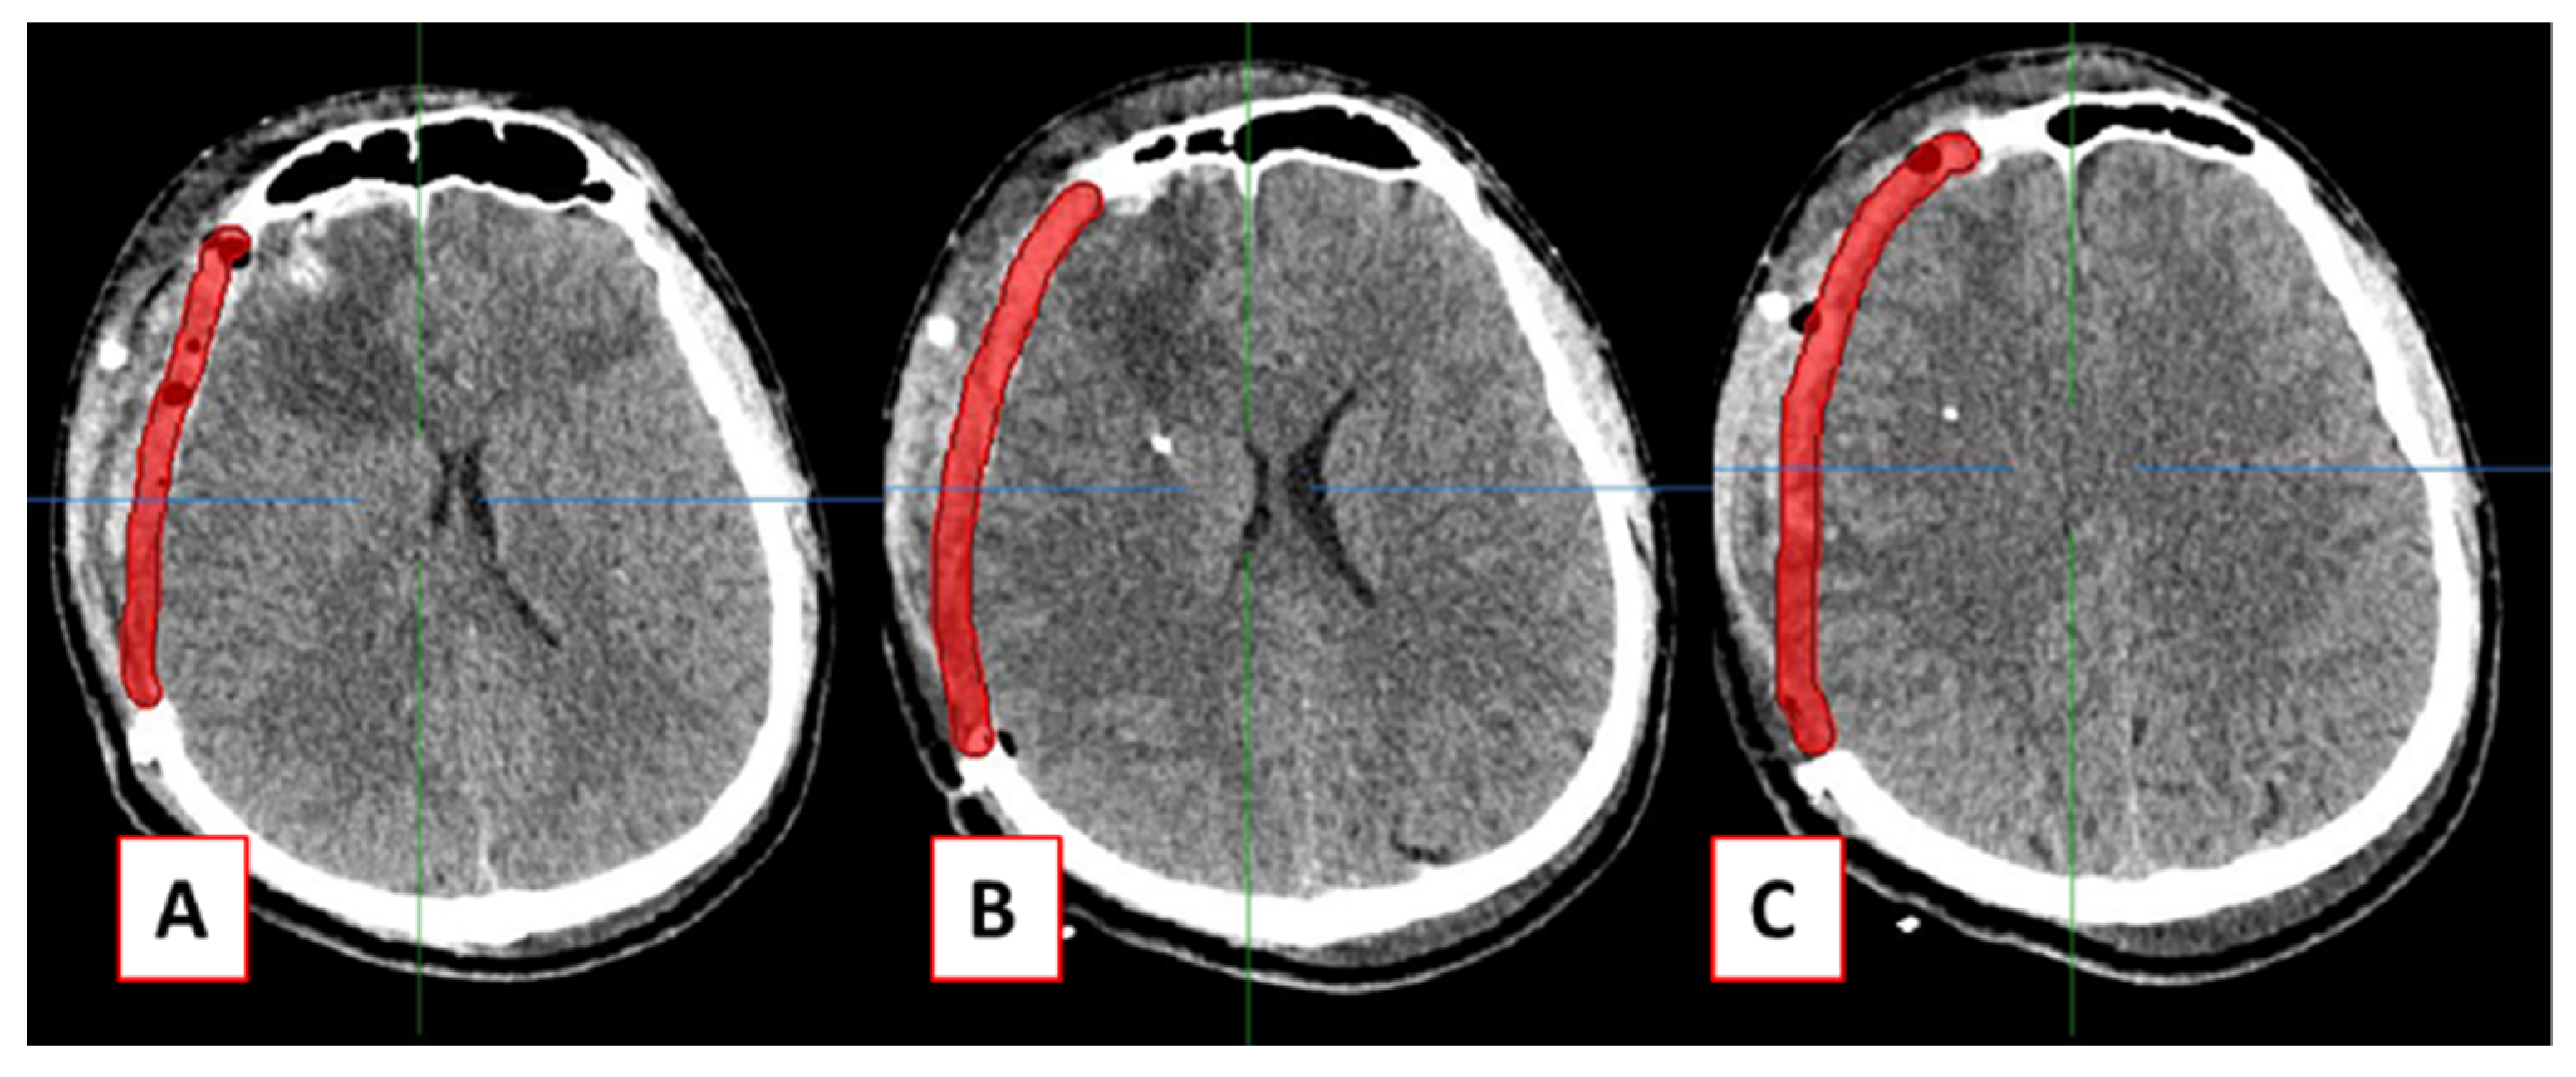

As an alternative to commercial 3-matic software, MITK was used to design the patient-specific cranial implant using a shape-based interpolation method. After the CT data of defected skull were loaded, a new “Segmentation” was created to design the cranial implant. Next, the paint size 14 in the 2D Tools box (red rectangle) was used to draw the line along the defective skull, as shown in Figure 2.

Figure 2.

The “Paint” tool was used to draw the line along defective skull.

A line was drawn to represent the thickness of the implant to cover the defect. The first line to be drawn may be selected from the most top or most bottom of the CT data axial slices, following which the same line is drawn on every tenth or fifth slice. In this example, the total axial slices within the defective area are 132 slices (slice no 91 to 223). Starting with slice no 91, every tenth slice was selected to draw the line for implant design, one by one, until slice 221, which were 91, 101, 111, 121, 131, 141, 151, 161, 171, 181, 191, 201, 211, and 221. The total number of slices involved for shape-based interpolation was 14 slices. Figure 4 shows the example of a line drawn in axial slice numbers 151, 161, and 171.

Figure 4.

Slices (A) 151, (B) 161, and (C) 171 of every tenth slice.